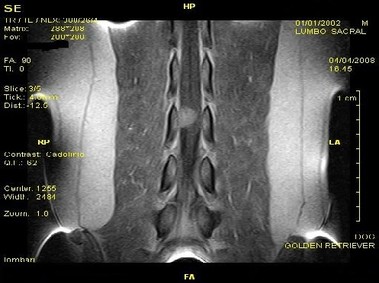

В настоящее время МРТ является наиболее предпочтительным методом визуализации любых мягких тканей, особенно для визуализации травм и патологий центральной нервной системы и суставов. Особенности Vet-MR позволяют использовать данный метод визуализации также в сфере ветеринарии.

Vet-MR специально разработана для визуализации небольших животных и является результатом внимания к деталям при разработке магнита, катушки и электронных компонентов, обеспечивая высокое качество экономически эффективной и простой в использовании МРТ в сфере ветеринарии.